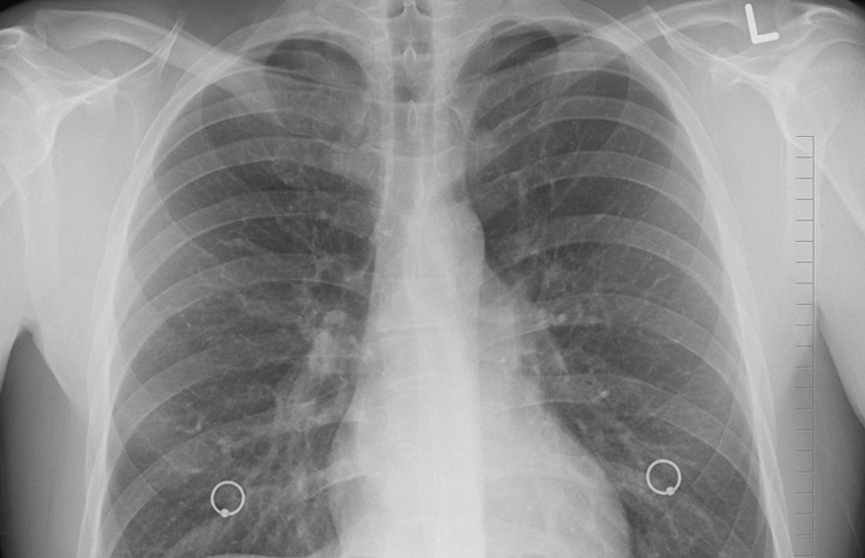

The Sun: Миру грозит эпидемия мутировавшего туберкулеза

Британские врачи предупреждают о новой форме туберкулеза, сообщает издание The Sun.

Согласно имеющейся информации, речь идет о мутировавшей форме болезни. Главное отличие – отсутствие характерных симптомов данного заболевания.

Такое отличие может представлять серьезную угрозу, поскольку ни заболевший, ни окружающие не могут заподозрить наличие инфекции, что повышает риски заражения.

Сообщается, что новая разновидность туберкулеза уже распространилась достаточно сильно. В частности, у 4 из 5 человек, у которых он был выявлен, не имеют симптомов болезни.

Фото: Pixabay